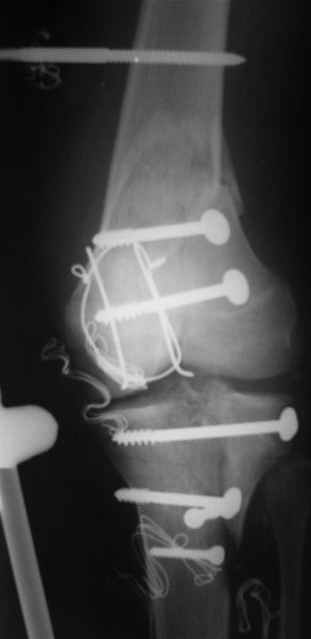

ET> обработку и внешнюю фиксацию, картинки в приложении.

Вид раны на сегодня...

4 cутки после травмы.

Спасибо за комментарии. Травма тяжелая с проблематичным прогнозом для функции коленного сустава( изначально травма разгибательного аппарата с последующим частичным некрозом собственной связки надколенника и о обнажением рефиксированного фрагмента бугристости большеберцовой кости, дефектом центрального отдела суставной поверхности большеберцовой кости и медиального отдела капсулы сустава).